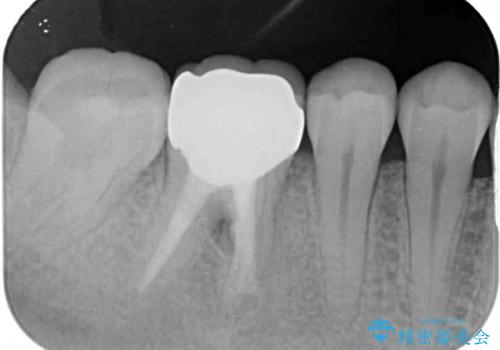

腫れていた歯茎は根管治療後に解消され、適合の良いセラミッククラウンを装着することができました。